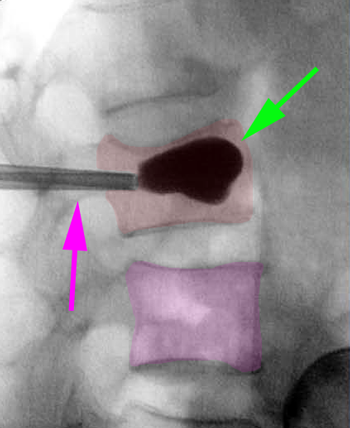

Διαδερμική κυφοπλαστική, ακτινοσκόπηση. Η ειδική βελόνη εισέρχεται διαδερμικά στο σώμα του σπονδύλου (φούξια βέλος) και γίνεται έκπτυξη μπαλονιού το οποίο ανατάσει το οστεοπορωτικό κάταγμα (αριστερά). Κατόπιν πραγματοποιείται έγχυση ακρυλικού πολυμερούς στο σώμα του σπονδύλου για να σταθεροποιηθεί το αναταχθέν κάταγμα (δεξιά).